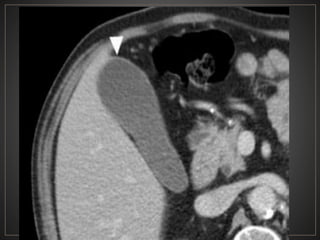

• #40 Serie de TC abdomen en fase portal, hacia topografia de coledoco se observa una lesion de morfologia redondeada, de bordes definidos, densidad liquido, con medidas de 59 × 53 × 41 ubicada entre la vesícula biliar la cual se encuentra colapsada y la cabeza pancreática.

• #44 TC corte axial de abdomen simple donde se observa hacia topografia de coledoco una imagen de morfoloia redondeada, de bordes definidos, con densidad liquido, en relacion a coledocele, asimismo se observa un lito en coledoco.

• #47 Axial ventana tejidos blando fase portal, se observan multiples imágenes de morfología ovalada, de bordes definidos, hipodensa, correpondiente a quistes intrahepaticos y un quiste grande extrahepatico - tipo IVa